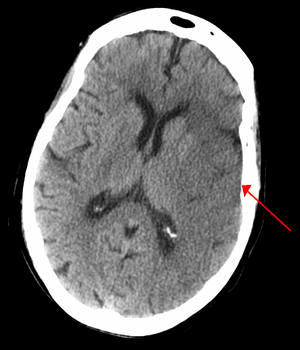

CT scan slice of the brain showing a right-hemispheric ischemic stroke (الجانب الأيسر من الصورة).